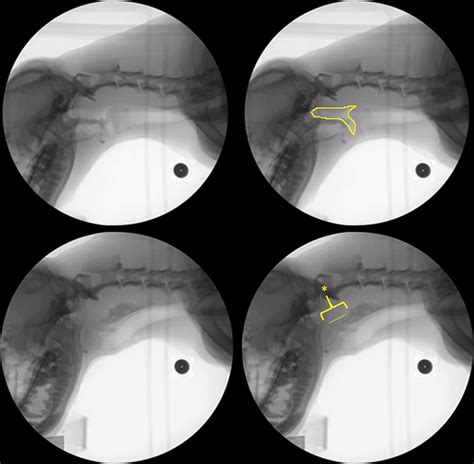

The Videofluoroscopic Swallow Study (VFSS), also known as a modified barium swallow, is a diagnostic procedure that uses fluoroscopy and a barium-based contrast material to visualize the swallowing process. This study helps identify the specific phase of swallowing that is impaired, whether it is the oral, pharyngeal, or esophageal phase.

During the study, the patient will be asked to swallow various consistencies of barium-coated food and liquids while being observed under fluoroscopy. This real-time imaging allows the healthcare team to assess the swallowing mechanism in detail.

The results of a Videofluoroscopic Swallow Study provide valuable information about the swallowing process. The healthcare team looks for various indicators, including:

• Aspiration: The entry of food or liquid into the airway, which can lead to pneumonia.

• Penetration: The entry of food or liquid into the laryngeal vestibule but not below the vocal folds.

• Residue: The remaining food or liquid in the mouth, pharynx, or esophagus after swallowing.

• Delay in swallow initiation: A delay in the start of the swallowing reflex.

• Reduced tongue base retraction: Inadequate movement of the tongue base, which can affect the clearance of food from the mouth.